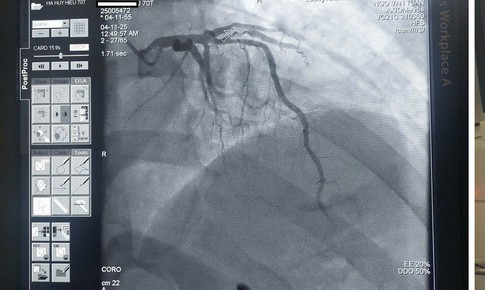

can thiệp đặt stent mạch vành

SKĐS - Mới đây, vào đêm 3/11, đội ngũ y bác sĩ của Bệnh viện Đa khoa khu vực Cẩm Phả (tỉnh Quảng Ninh) đã "hồi sinh sự sống" cho cụ ông Hà Huy H (70 tuổi, trú tại phường Mông Dương) bị nhồi máu cơ tim cấp nguy kịch...